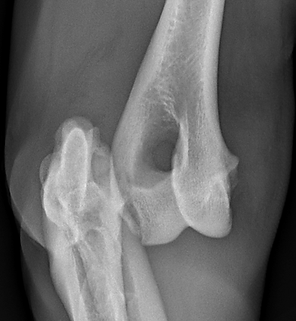

Once the patient is stable, X-rays are essential. While most dislocations are easy to see on radiographs, isolated ligament injuries may be missed.

In these cases, stress radiographs — taken while applying a controlled force to the joint — are often necessary to demonstrate instability.